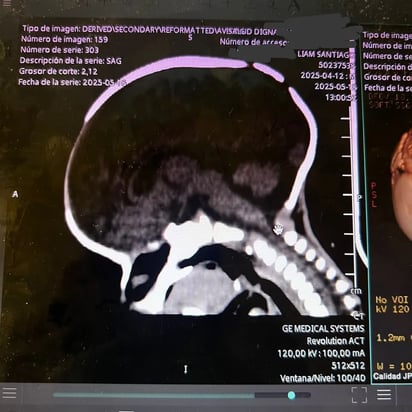

Su nombre es Santiago, tiene poco más de un mes de haber nacido y luego de una cita médica se le diagnosticó con craneosinostosis.

Esta es una condición en la que las suturas del cráneo de un bebé se cierra prematuramente, antes de lo que debería, impidiendo su crecimiento como debería ser.

La craneosinostosis puede afectar la forma de su cabecita y causar problemas en el desarrollo del cerebro, como: deformaciones craneales y faciales, aumento de presión intracraneal y problemas visuales.

Dicha condición es de cuidado, por lo que los primeros meses son ideales para tratarla, realizando una cirugía de su cabecita.